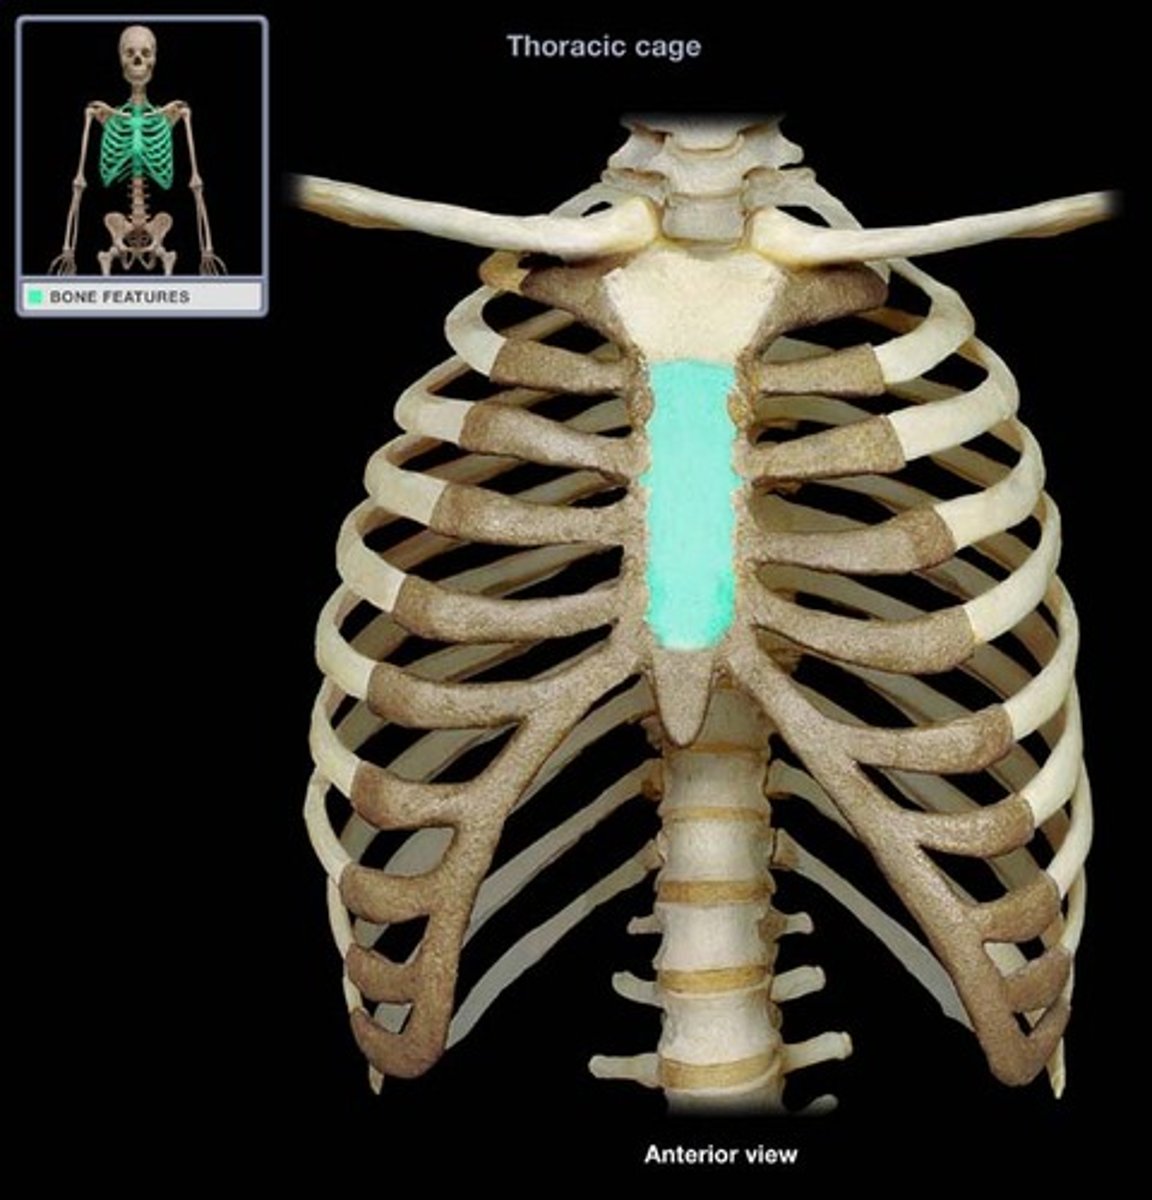

sternum

What is this bone?

manubrium

What is this structure?

body of sternum

What is this structure?

sternal angle

What is this structure?

clavicular notch